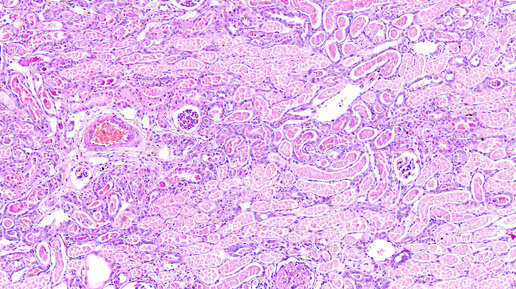

Распад опухоли встречается на поздних стадиях заболевания, когда злокачественное новообразование достигает значительных размеров. По своей сущности этот процесс представляет собой отмирание (некроз) раковых клеток из-за недостаточного кровоснабжения...